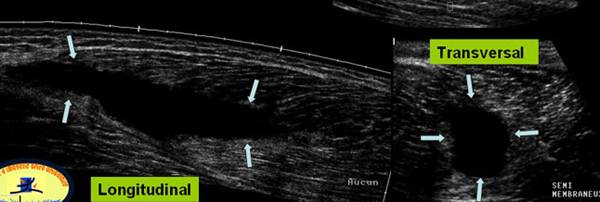

Antecedente de leziune a m. Ischio-gambieri cu persistenta unei jene la efort

Prezenta unei colectii fuziforme, bine delimitata, compresibila care va fi

Punctionata sub ghidaj ecografic